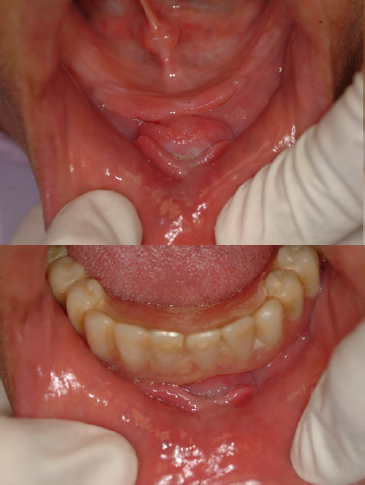

Epulis Fissuratum

• AKA: denture-induced fibrous hyperplasia, fibrous inflammatory hyperplasia

• Cause: ill-fitting denture

• Location: vestibule (maxilla or mandible), along the

denture border

•Clinical presentation: Arranged in elongated folds of tissue into which the

denture flange fits; • Surface ulceration within the folds is common

• Composed of dense fibrous connective tissue

• Treatment: surgical excision (scalpel vs CO2 laser -laser is better)

and reline then remake of denture